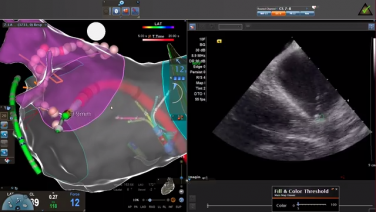

Intracardiac Echo Views During the AF Procedure with Brett Gidney, MD

In the EP Lab - ICE & Mapping During the PVC Case with Andrew Brenyo, MD